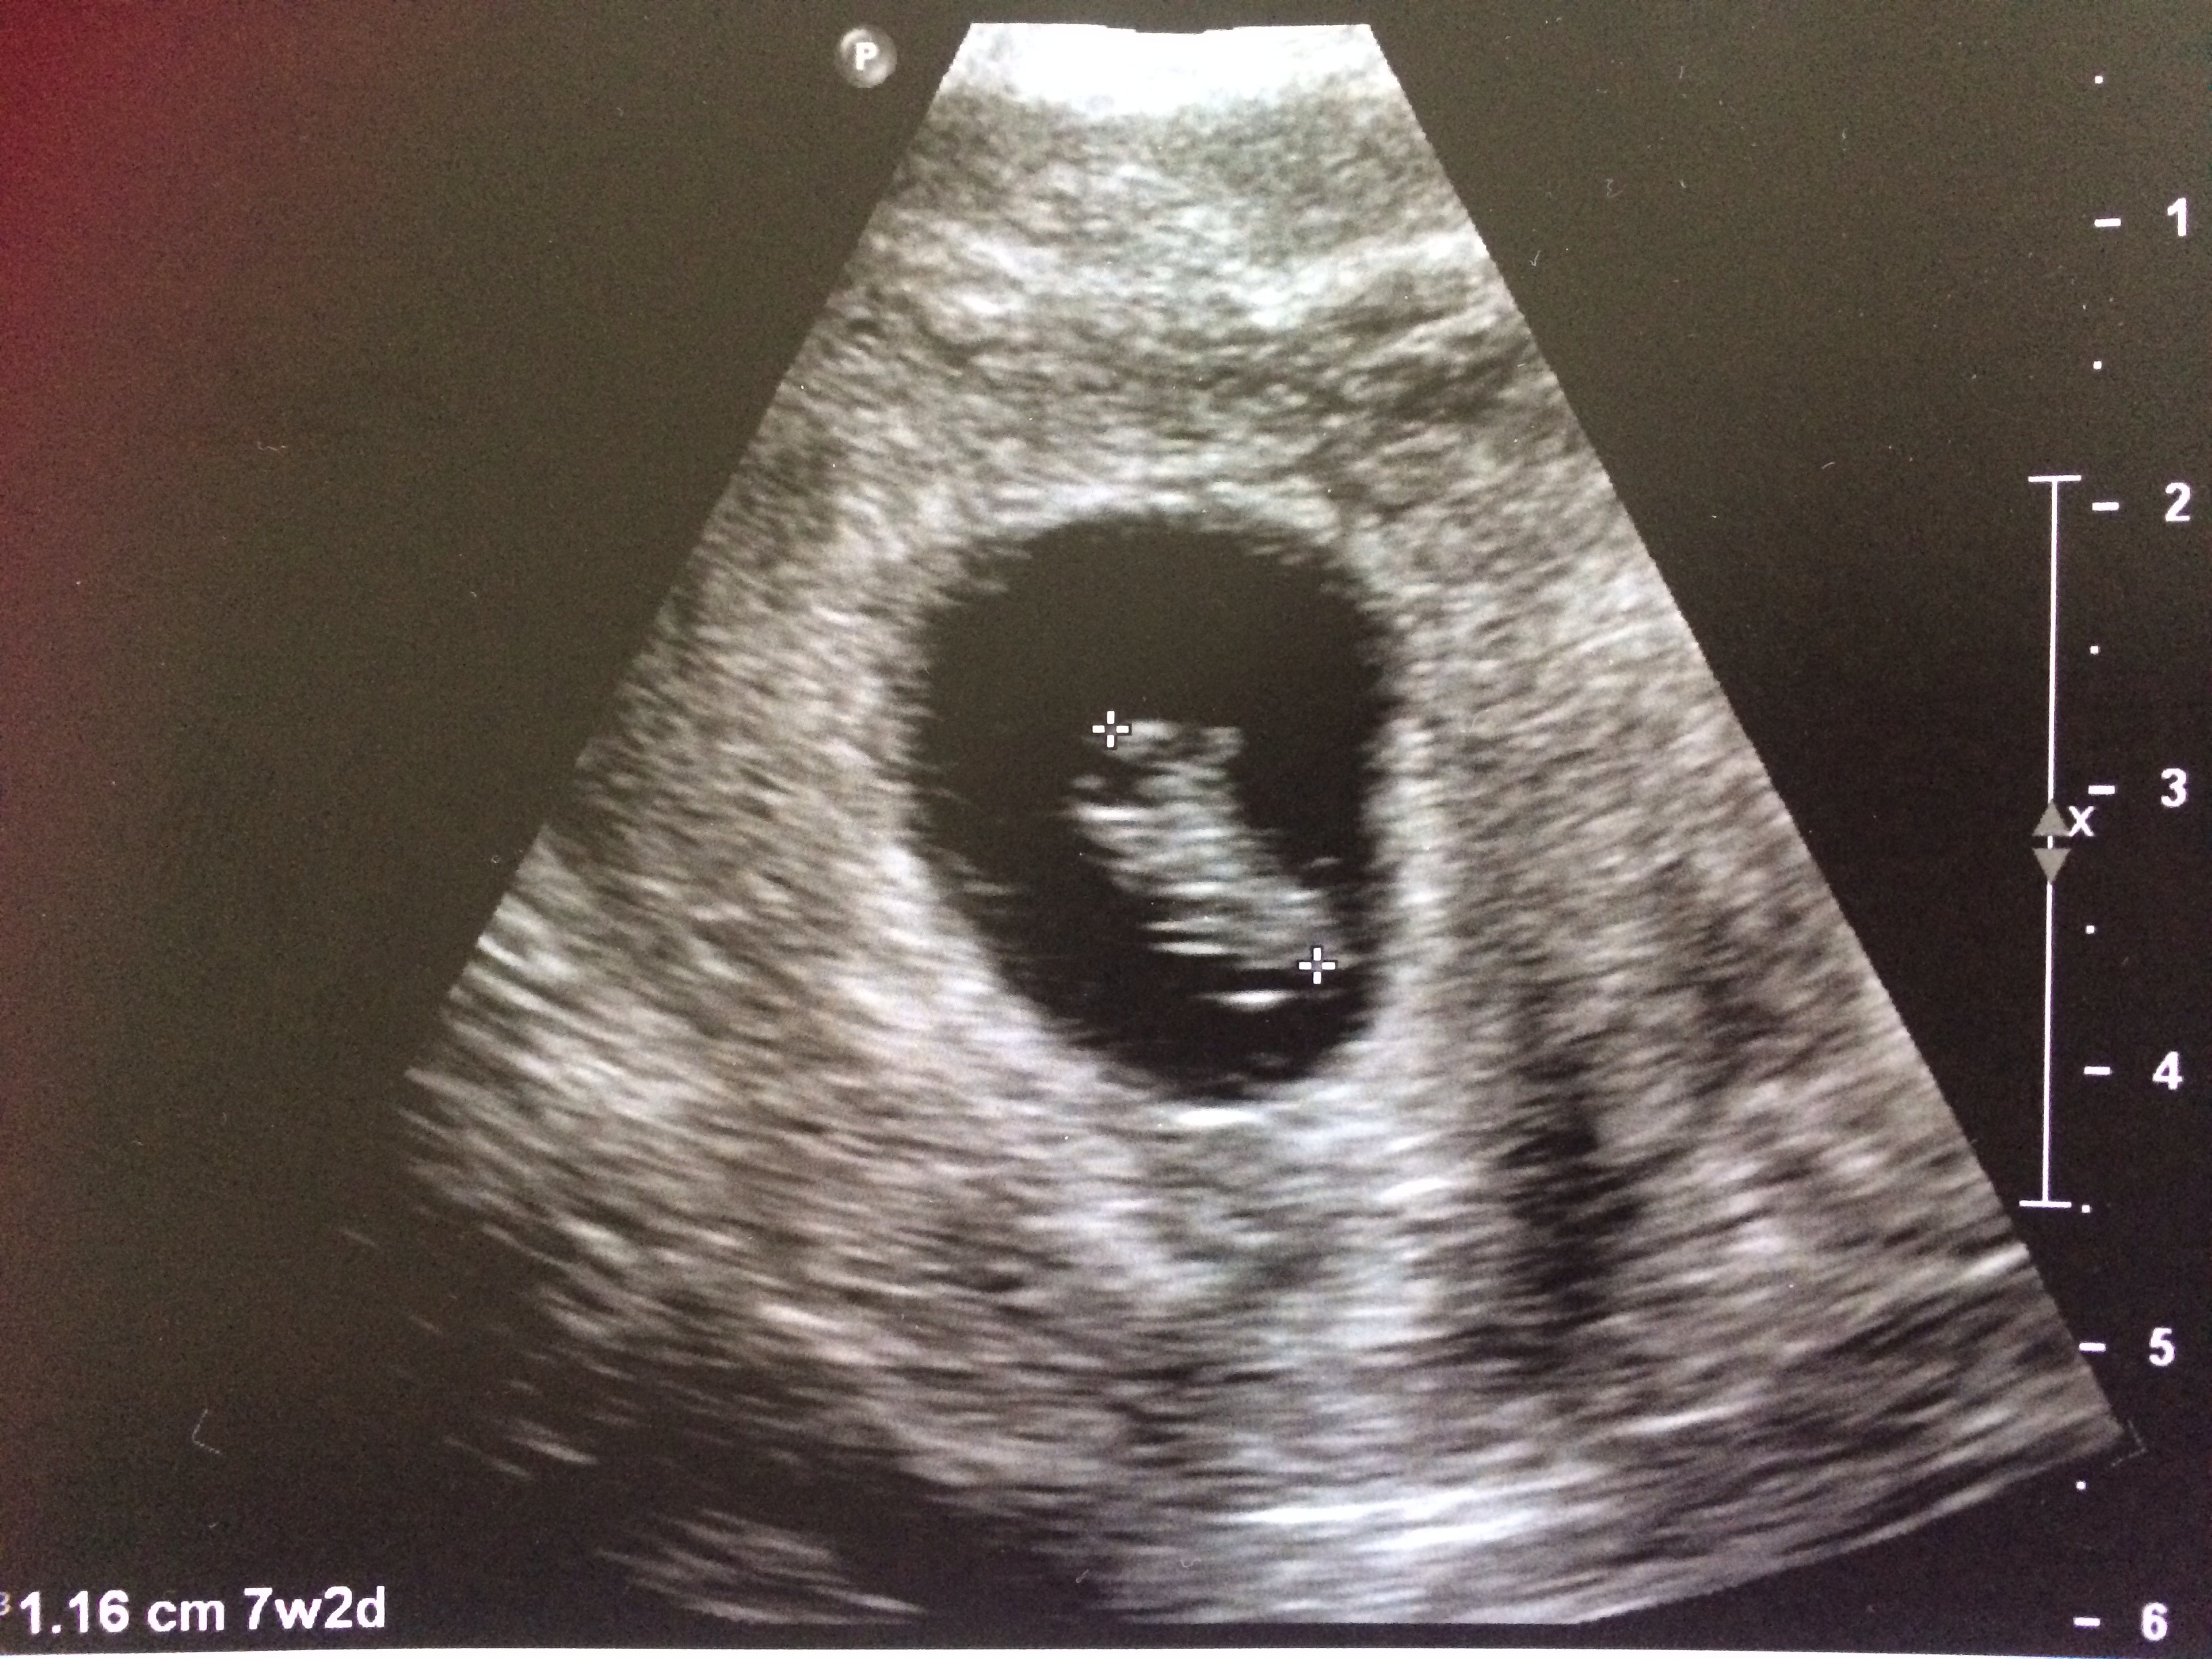

Well i guess i should introduce myself. This is my First pregnancy with the help of fertility medication and i had my first u/s today and measured right on track at 7w2d. The little ones heartbeat was 160bpm. Starting to feel more real! Meeting with my OB when we can hopefully hear the heartbeat at 9weeks. Hoping for a happy and healthy 9months.